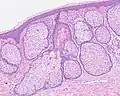

Sebaceous hyperplasia shares histopathological similarities with the typical architecture of the folliculosebaceous unit, but with larger and expanded sebaceous glands.[12][13]

H&E staining of biopsied lesion of sebaceous hyperplasia: Note the multiple, mature sebaceous lobules attached to the central dilated duct in the upper dermis.